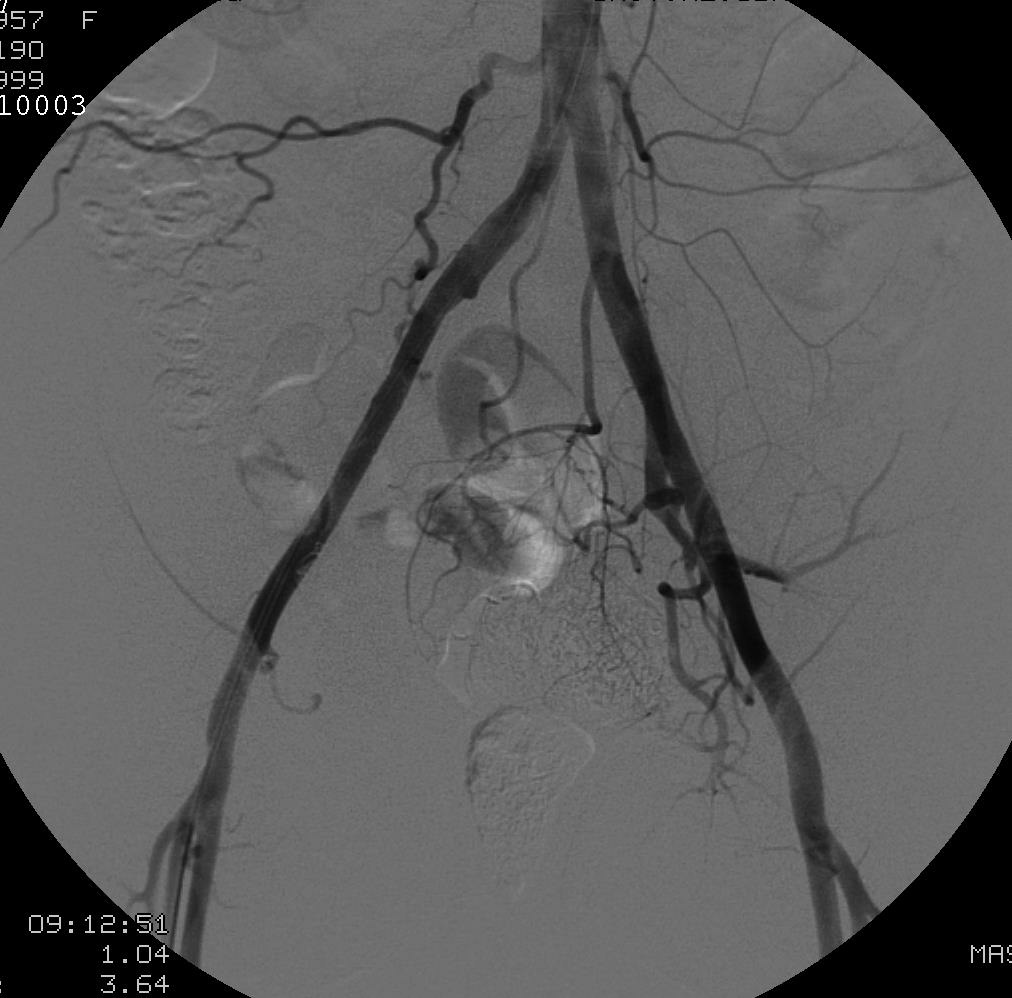

右侧腰动脉造影

选择性肠系膜下动脉造影

42F,复发性疼痛,双下肢肿胀,血尿;子宫切除史,卵巢切除史,所有盆腔血管术中结扎等

滋养动脉:右侧卵巢动脉,骶中动脉,双侧髂外动脉,左髂内动脉,右股浅动脉和右侧股深动脉等。

左髂内动脉造影显示大量畸形血管和明显单一扩张的引流静脉

经静脉栓塞

症状消失